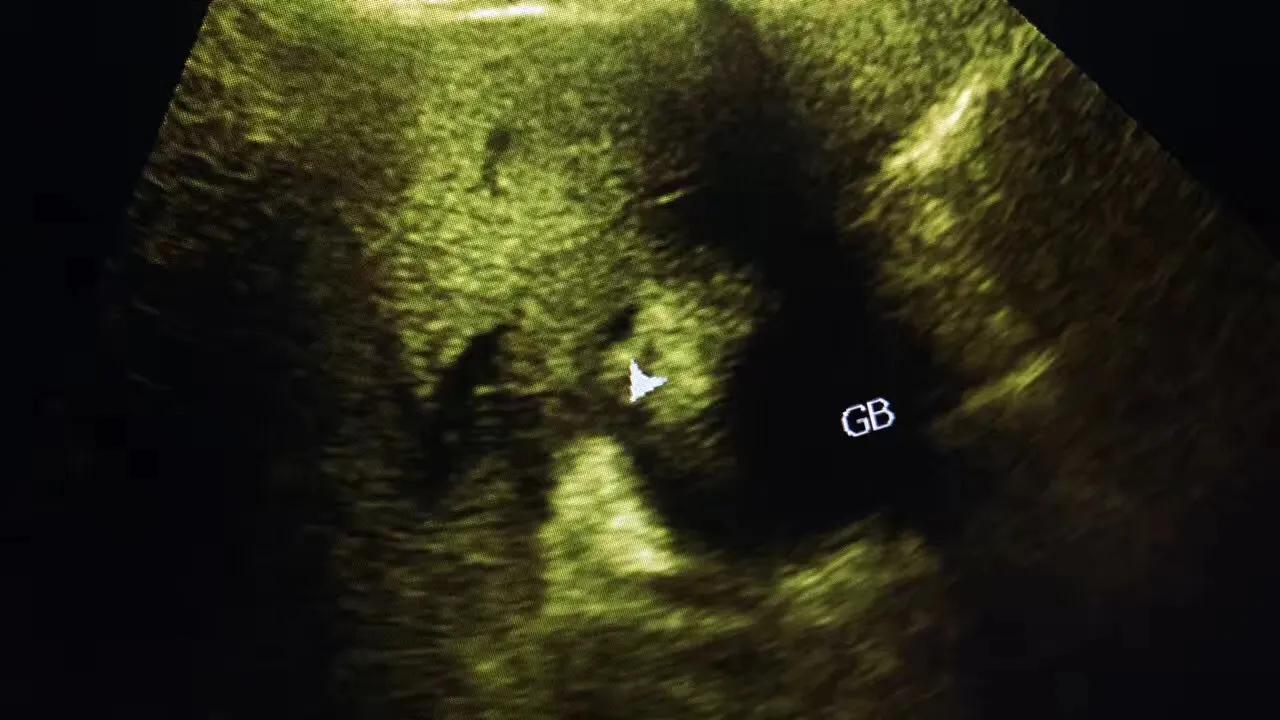

病例1.患者女性,57岁,胆囊颈部结石嵌顿继发急性胆囊炎!胆囊肿的像个茄子!

病例2.患者女性,63岁,胆囊颈部结石嵌顿继发急性胆囊炎胆囊穿孔!急诊手术证实胆囊穿孔!